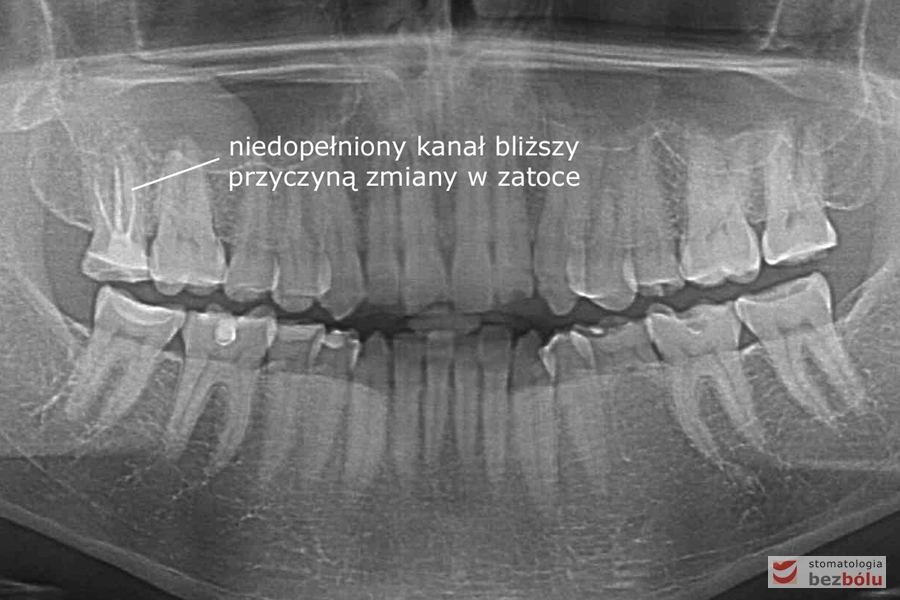

Diagnostyka radiologiczna - przetrwały ząb mleczny w żuchwie, brak zawiązka stałego

Diagnostyka radiologiczna – przetrwały ząb mleczny w żuchwie, brak zawiązka stałego

Kontrola radiologiczna - ocena szczelności wypełnionych kanałów korzeniowych

Kontrola radiologiczna – ocena szczelności wypełnionych kanałów korzeniowych